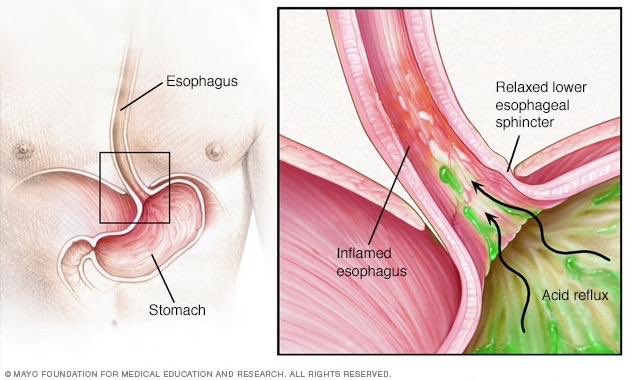

متى تزور الطبيب ؟ إذا كنت تعاني من ألم في الصدر، خاصة إذا كنت تشعر أيضًا بضيق في التنفس أو ألم في الفك أو الذراع